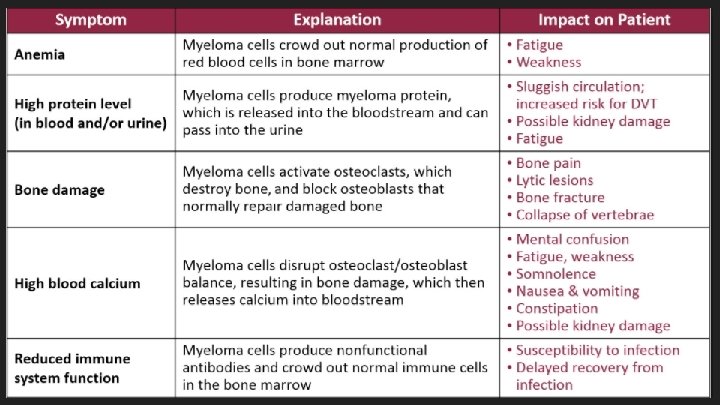

Multiple Myeloma Neoplastic monoclonal proliferation of bone marrow plasma cells characterized by the presence of : ○ monoclonal protein in serum and/or urine ○ lytic bone lesions ○ plasma cell accumulation in the bone marrow

Pathophysiology ● MM cells produce abnormal immunoglobulins ● Bind to bone marrow stromal cells which stimulate growth and proliferation of MM cells within the bone marrow

Bone Pain ● Due to the expanding population of plasma cells ● Most common symptom (70%) ● Precipitated by movement ● Bone disease: ○ Activation of osteoclasts and suppression of osteoblast ○ Lytic lesions (maybe palpable) ○ Hypercalcemia ○ Pathological fractures ○ Vertebral collapse – spinal cord compression

Renal failure ● 25% of patients. 50% have some kind of renal damage. ● Causes ● ● ● ● Cast nephropathy Light chain toxic effects Hypercalcemia Glomerular deposition of amyloid Hyperuricemia Recurrent infections Proteinuria ● ● Bence - Jones proteinuria Non – selective proteinuria if glomerular damage

Normocytic Normochromic Anaemia ● ~80% of patients ● Lethargy, weakness, dyspnea, pallor, tachycardia ● Causes ● ● ● Replacement and extension of normal marrow by myeloma cells Inhibition of haematopoiesis by tumour factors Decreased erythropoietin production by the kidney

Hypercalcemia ● ● ● Stones ● Renal calculi ● Psychiatric moans ● Confusion ● Mental disturbances ● Depression ● Lethargy Polyuria Polydipsia Muscle weakness Bones – bone pain Abdominal groans ● Constipation ● Pancreatitis ● ● ●